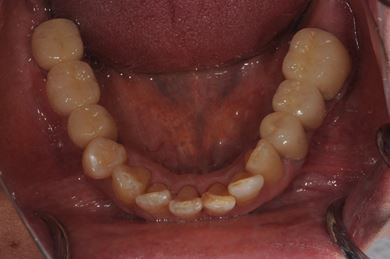

抜歯即日スピードインプラント治療+セラミック治療

| 性別/年齢 | 女性 / 49歳 | ||||||||||||||||||||||||||||||||

| 主訴 | 左奥歯のつめものが取れている所を治療したい。 | ||||||||||||||||||||||||||||||||

| 治療方針 | 抜歯と同時にインプラント埋入を行い、治療期間を短縮する。上前歯部、骨再生法によりインプラント治療を可能にする。 | ||||||||||||||||||||||||||||||||

| 治療内容 | インプラント4本(抜歯即日スピードインプラント、テンポラリーインプラント+仮歯)、メタルボンドセラミックブリッジ12本、メタルボンドセラミッククラウン3本(メタルボンド用土台1本) | ||||||||||||||||||||||||||||||||